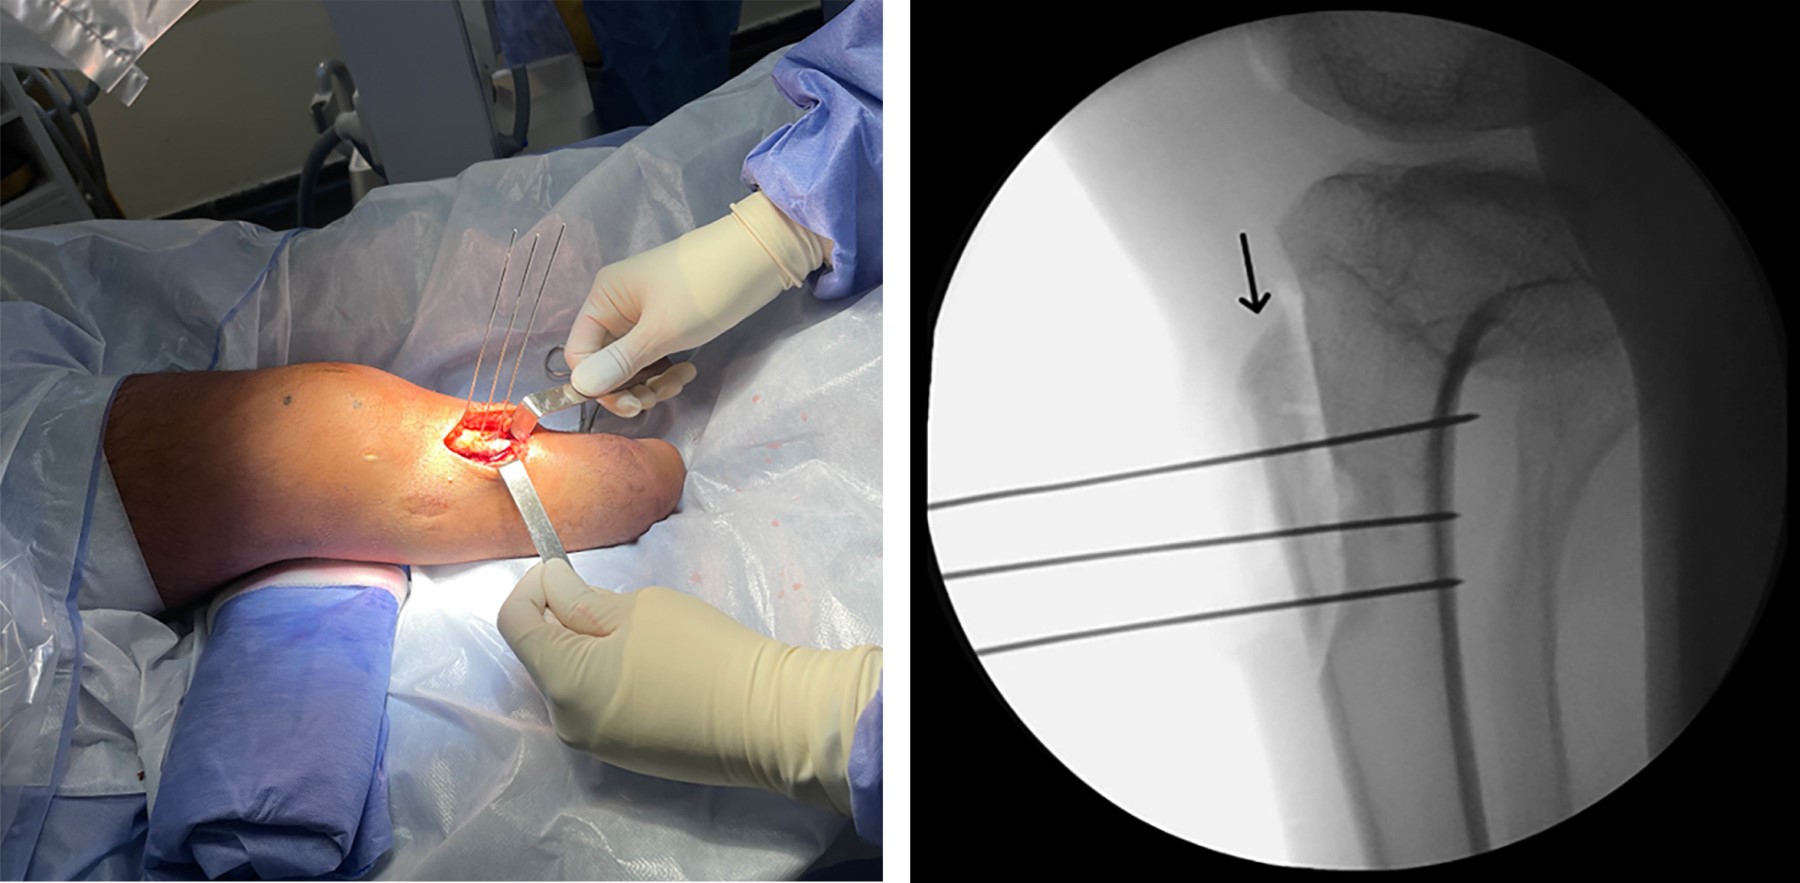

La inestabilidad patelofemoral es una condición multifactorial que abarca un espectro de manifestaciones que van desde subluxaciones hasta luxaciones completas de la rótula. Desde el punto de vista etiológico, puede originarse a partir de diversas anomalías anatómicas, incluyendo la alineación de las extremidades, la morfología ósea de la articulación patelofemoral y la integridad de los estabilizadores estáticos y dinámicos. Los pacientes con amputación por debajo de la rodilla tienen un mayor riesgo de experimentar inestabilidad patelofemoral. Este informe describe un caso que involucra a un paciente con inestabilidad patelofemoral y una amputación transtibial, tratado de manera efectiva con realineación distal y estabilización patelar lograda mediante la reconstrucción del complejo patelofemoral medial (CPFM).

Figura 2